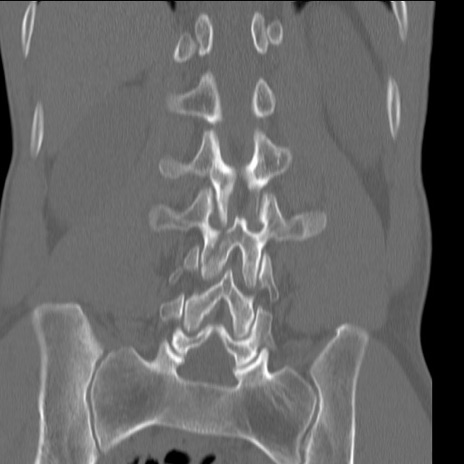

症例3 腰椎CT(冠状断像)

腰椎CT